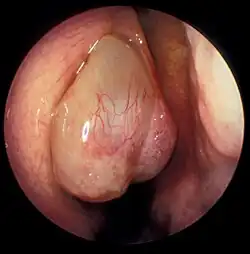

Nasal polyp

| A nasal polyp | |

Nasal polyps are noncancerous growths within the nose or sinuses.[1] Symptoms include trouble breathing through the nose, loss of smell, decreased taste, post nasal drip, and a runny nose.[1] The growths are sac-like, movable, and nontender, though face pain may occasionally occur.[1] They typically occur in both nostrils in those who are affected.[1] Complications may include sinusitis and broadening of the nose.[2]

Nasal polyps can be seen on physical examination inside of the nose and are often detected during the evaluation of symptoms. On examination, a polyp will appear as a visible mass in the nostril.[5] Some polyps may be seen with anterior rhinoscopy (looking in the nose with a nasal speculum and a light), but frequently, they are farther back in the nose and must be seen by nasal endoscopy.[12] Nasal endoscopy involves passing a small, rigid camera with a light source into the nose. An image is projected onto a screen in the office so the doctor can examine the nasal passages and sinuses in greater detail. The procedure is not generally painful, but the person can be given a spray decongestant and local anesthetic to minimize discomfort.[13]